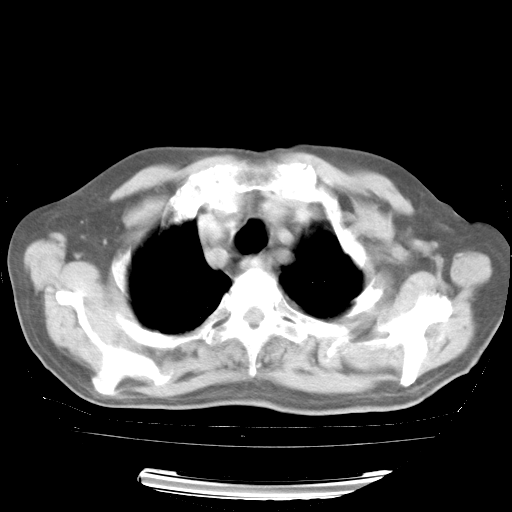

今天部分检查

轻微咳嗽,无痰,(体温正常时)R20次/分,P75次/分,双肺底、腋下可闻及少量捻发音。下肢轻度浮肿。

血常规:白细胞9.11×109/L,N0.92,L5.64,血小板39.2×109/L,HB148g/L,ESR2mm/H。

尿常规:潜血+

血生化:总蛋白69.71g/L,白蛋白38.40g/L,球蛋白31.31g/L,CRP27.9mg/L,尿素氮11.98mmol/L,肌酐106μmol/L,乳酸脱氢酶1099 U/L,肌酸激酶108U/L,CK-MB 61U/L。

腹部B超:胆囊壁增厚,肝、胆、胰、脾、肾无异常,肠系膜淋巴结、腹膜后淋巴结无增大。

ECG:右心室增大

心脏超声检查:无右心室增大。

增加治疗:异烟肼、利福平、乙胺丁醇,静滴左氧氟沙星、参麦注射液。甲强龙从80mg暂减为40mg。

强的松3月1日改为10mg qd,4月1日改为10mg qod。3月份以前的减量过程和环磷酰胺疗程需等明天查看记录(我岳父自己做的记录在他家里)。